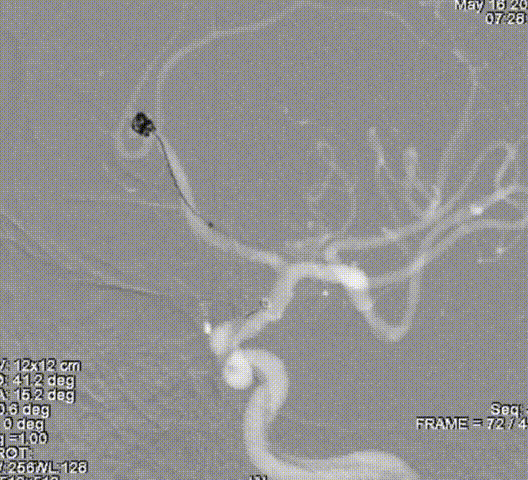

栓塞过程

先通过微导管填塞成篮圈,输送支架到左侧大脑中动脉下干并释放,使支架覆盖动脉瘤开口。依次填入Jasper®SS弹簧圈多枚。

术后即刻影像